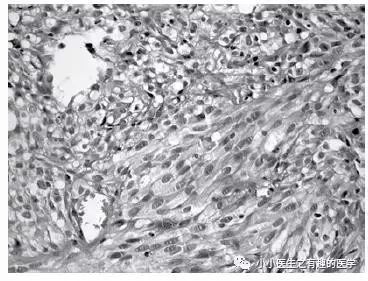

行动脉血栓内膜剥脱术,然而结果示黏液性梭形细胞肉瘤。

Surgical thromboendarterectomy revealed a high-grade myxoid spindle cell sarcoma.

是的,这不是肺栓塞,这是肺动脉内膜肉瘤。这不是扯蛋肺栓塞,这是扯蛋肺动脉肿瘤。扯蛋是肯定的,然而,血栓且不肯定。

好大的一条血栓!然而,最终做了手术,病理如下:

五颜六色的,好好看啊。然而,this is 肺动脉内膜肉瘤。仔细看看,不对。

病理:Intimal sarcoma of the pulmonary artery,肺动脉内膜肉瘤。

病理:肺动脉内膜肉瘤。

Macroscopic (Panels G and H) and microscopic (Panel I) examination revealed the presence of an intimal sarcoma of the pulmonary artery.

术后病理:肺动脉内膜肉瘤。

Histopathologically, the surgical specimen was not found to be thrombotic tissue but rather an intimal sarcoma of the pulmonary artery.

术中只见肿瘤,未见血栓。病理:肺动脉内膜肉瘤。

Based on the above histopathological findings, a diagnosis of pulmonary artery intimal sarcoma was made.